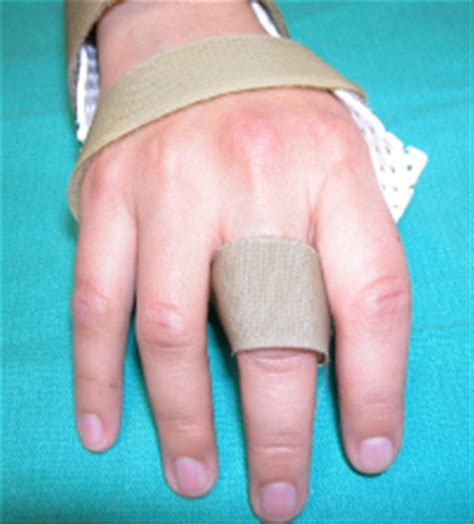

• Immobilization with a splint or brace to protect the injured area and promote healing.

Conservative treatment is often effective for mild to moderate injuries, allowing the sagittal bands to heal over time. However, it may take several weeks to months for a full recovery.